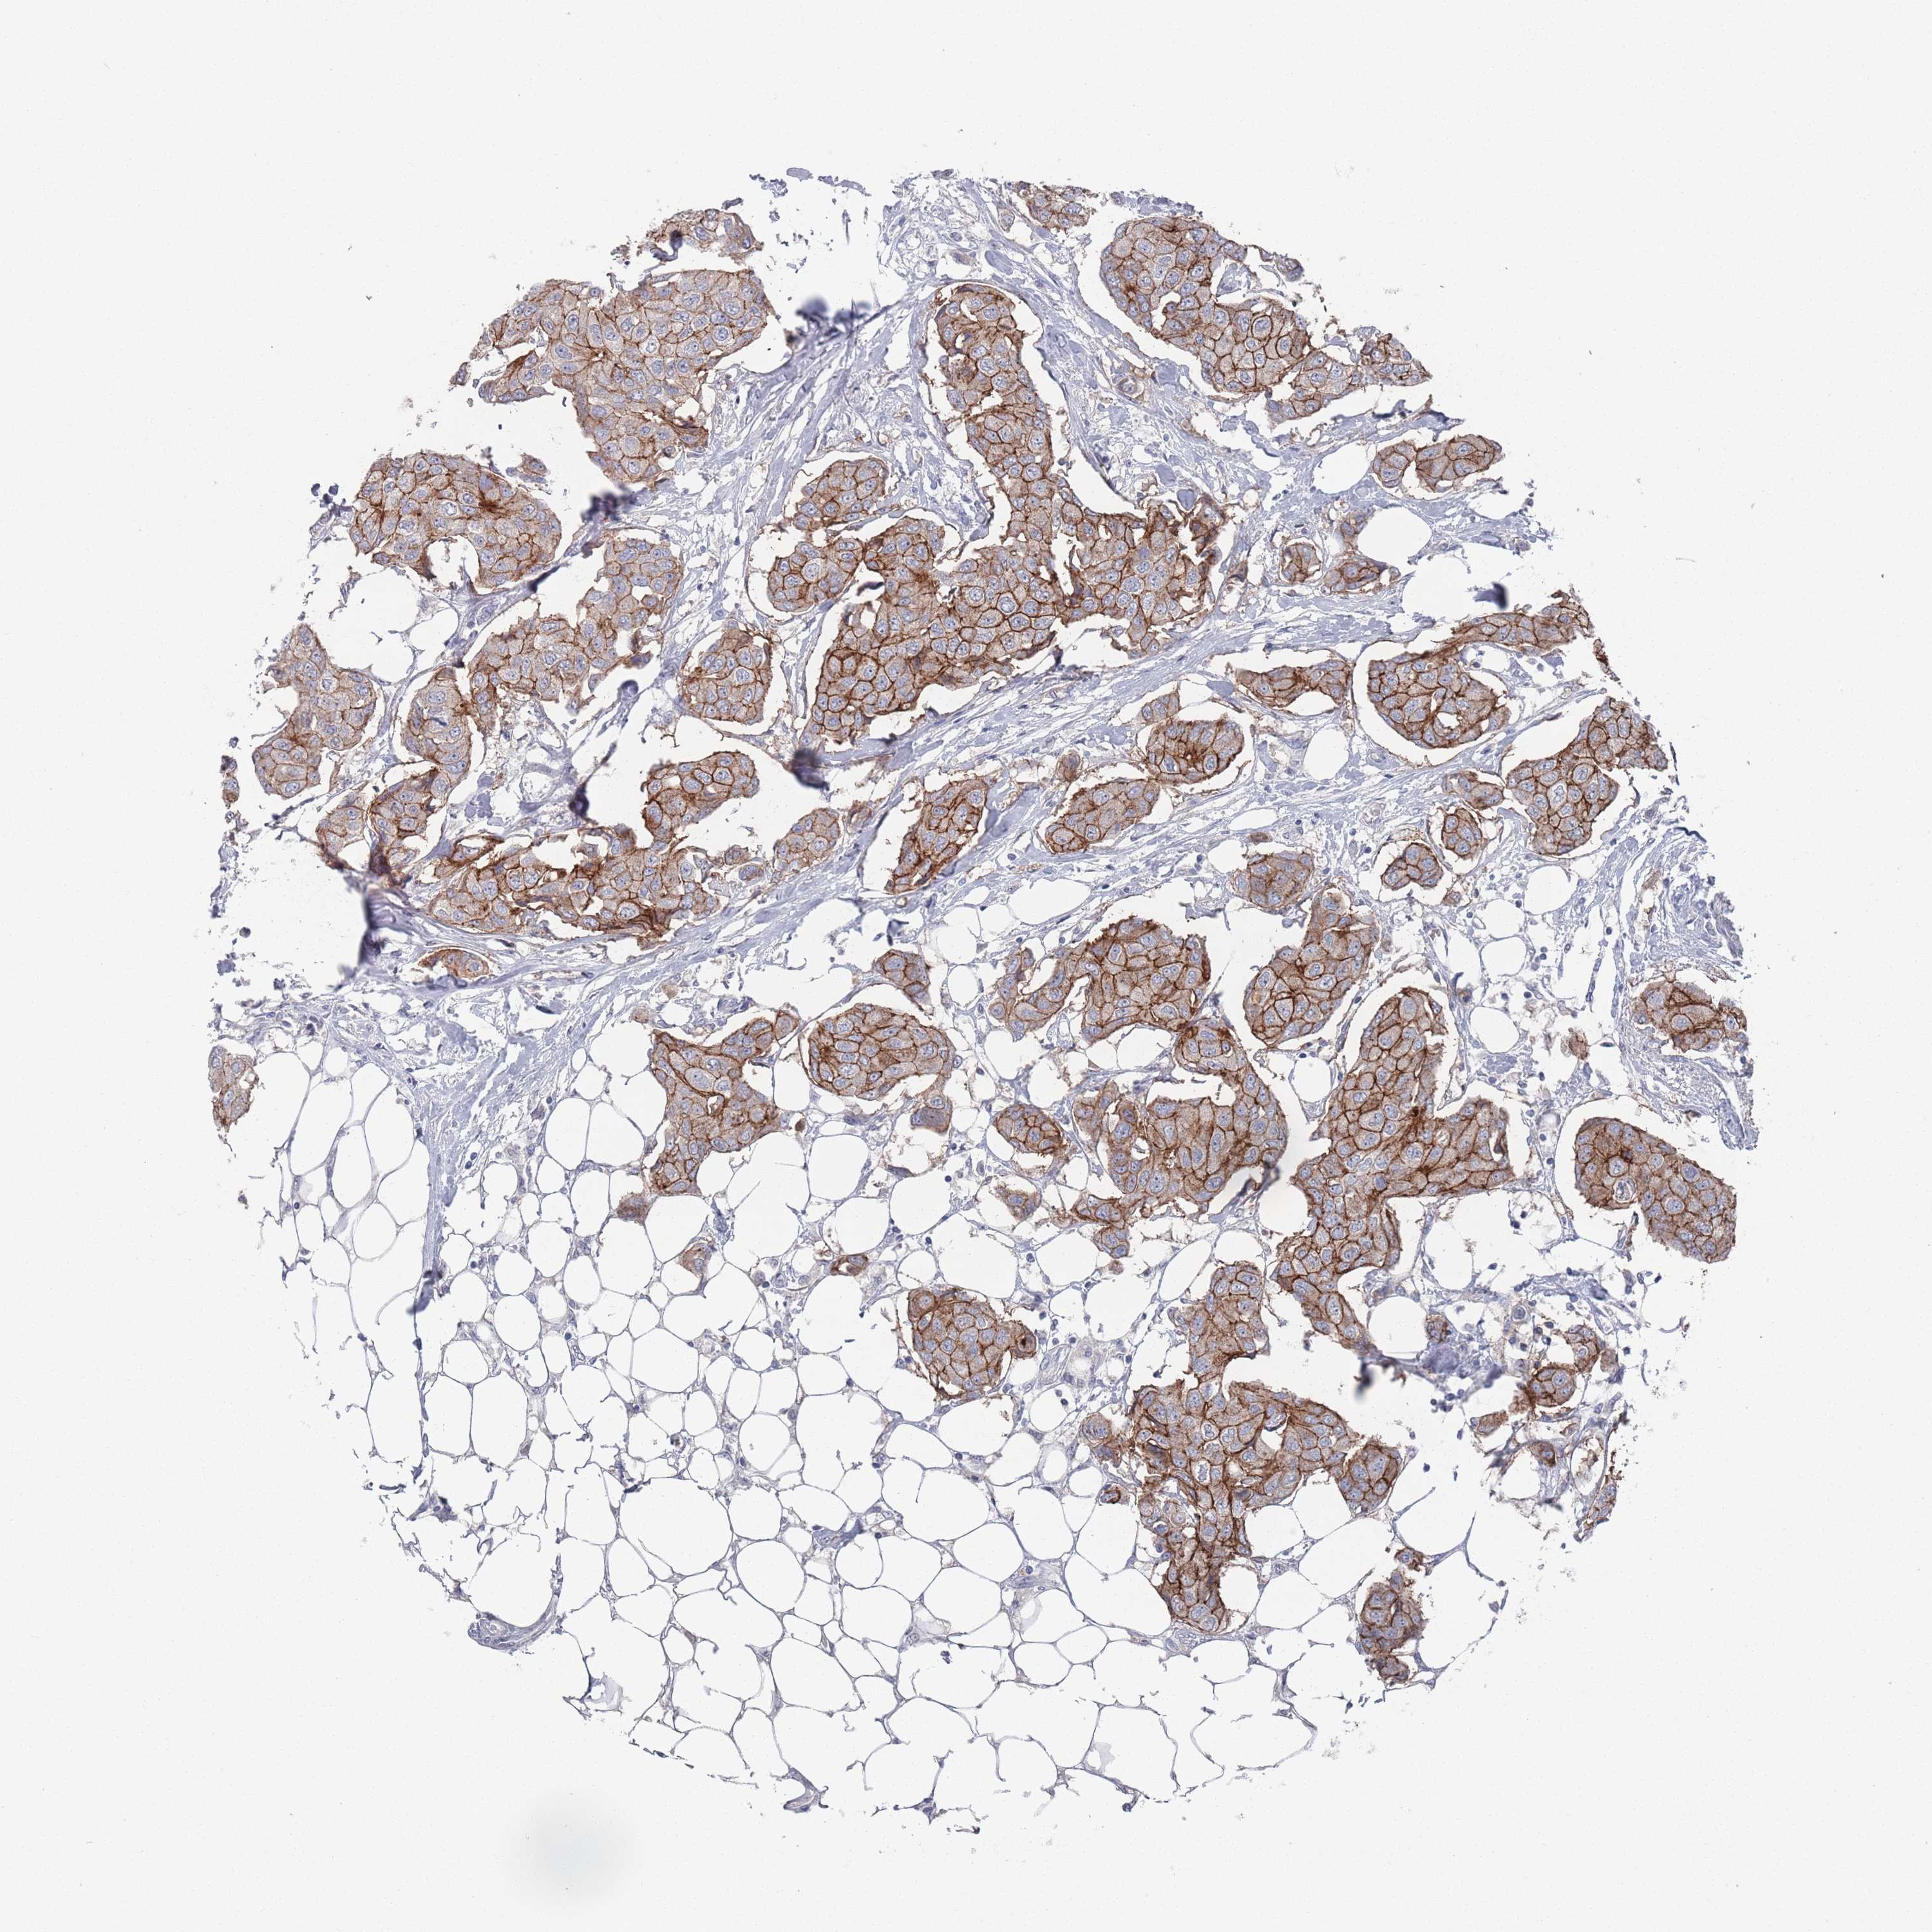

CANCER BREAST CANCER Show tissue menu

BRCA TCGA BRCA VALIDATION PROTEIN EXPRESSION

PROM2 is potential prognostic, high expression is unfavorable in Breast Invasive Carcinoma (TCGA)